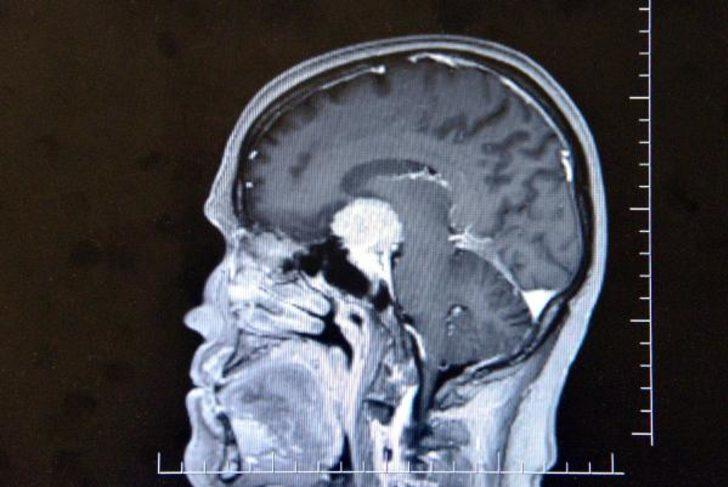

Altun tarafından yapılan muayene ve tetkiklerde Gül'ün beyninde ceviz büyüklüğünde tümör olduğu ve gözündeki sorunun tümörden kaynaklandığı tespit edildi.

Hastamız görme şikayetiyle ilgili birçok yere gitmiş ancak hastalıkla ilgili bir teşhis konulamamış. En son çekilen filminde ana şah damarlarını tamamen saran, görme sinirini tamamen kapatan, solunumla hayat merkezinin önünde geniş bir kitle olması üzerine hasta tarafıma geldi. Hastayı değerlendirdikten sonra endoskopik yöntemle kamera eşliğinde burundan girerek ceviz büyüklüğünde, 3,5 santim genişliğindeki kitleyi almaya karar verdik. Hastamız tüm riskleri kabul etti. Tabi burada önemli olan ana damarlar üzerinde geçmesi, ana damarlarını sarması, görme sinirinin üzerinde olması ve solunum merkezine doğru ilerlemesi bir risk faktörüydü. Biz bununla ilgili gerekli tedbirlerimizi aldıktan sonra ameliyata girdik."

"Ameliyatta başarılı bir şekilde gerçekleşti, herhangi bir görme sinirinde, ana damarlara veya solunum hayat merkezine dokunmadan tümörü tamamen burundan temizledik. Hastamız gayet iyi rahat. Beynin orta yerinde taban bölgesinde dediğimiz, 3,5 santim ebadında, ceviz büyüklüğündeki tümörümüz solunum hayat merkezinin önünü kaplaması ve oraya doğru ilerlemesi,sağ ana damarlara doğru ilerleyip tamamen içerine alması ve hipofiz bezini alttan yukarı doğru sarması, bu ebada ulaşması milyonda bir oranda gözükür. Biz bu tümörü, burundan girilerek endoskopik yöntemle tamamen ana damarlara herhangi bir zarar vermeden çıkarttık.''